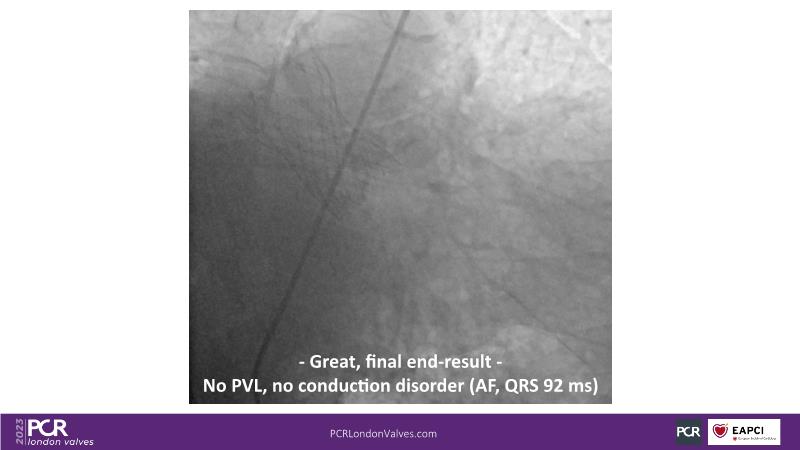

Defying complexity: achieving optimal TAVI procedural outcomes in challenging anatomies with the new Evolut FX

Watch this session to understand factors to consider when deciding on valve selection, recognize the significance of device choice and implantation technique in redo-TAVI, and acquire insights into anticipating challenges associated with implanting a bicuspid valve, large anatomy, and a horizontal aorta.

- To learn what to consider when determining valve selection

- To appreciate the importance of device choice and implantation technique in redo-TAVI

- To learn how to anticipate the challenges of implanting a bicuspid valve, large anatomy, horizontal aorta